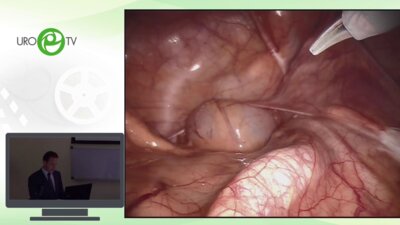

Международная конференция с «живой» хирургией ​​​​​​​«Лечение рака простаты: перемены неизбежны»